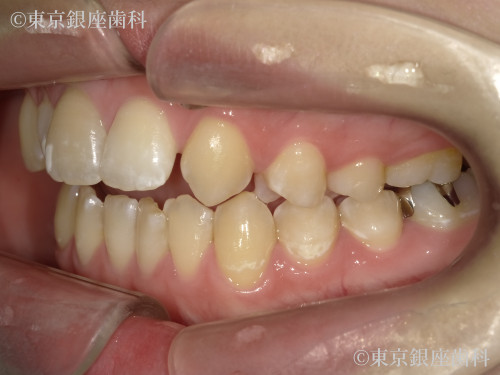

Before

疾患 矯正

施術内容 矯正

インビザライン:コンプリヘンシブパッケージ